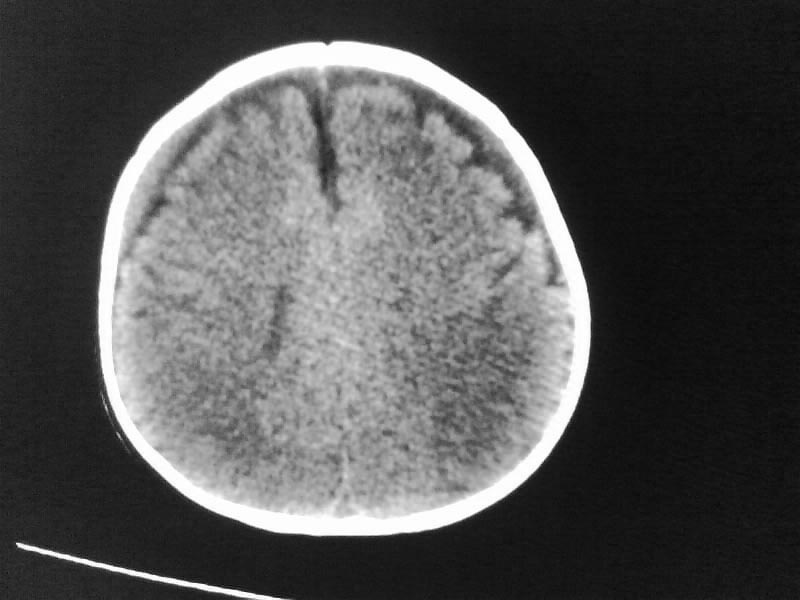

以下是引用随光逐影在2009-4-15 17:59:00的发言:[br]1)右侧额颞顶部硬膜下血肿。2)外部性脑积水。